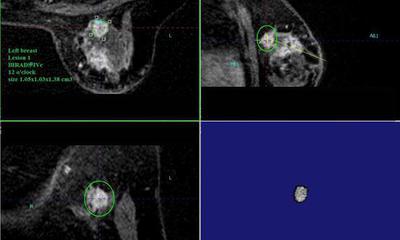

乳房專用型磁振造影有助於避免篩檢期間癌

術前就要讓腫瘤無所遁形 《乳房磁振造影適應症之術前評估篇》

隆乳女性得了罕見的乳房惡性葉狀瘤 《乳房磁振造影適應症之—隆乳者篩檢、顯示病灶特點》

善用乳房專用型磁振造影 避免乳癌術後殘餘癌